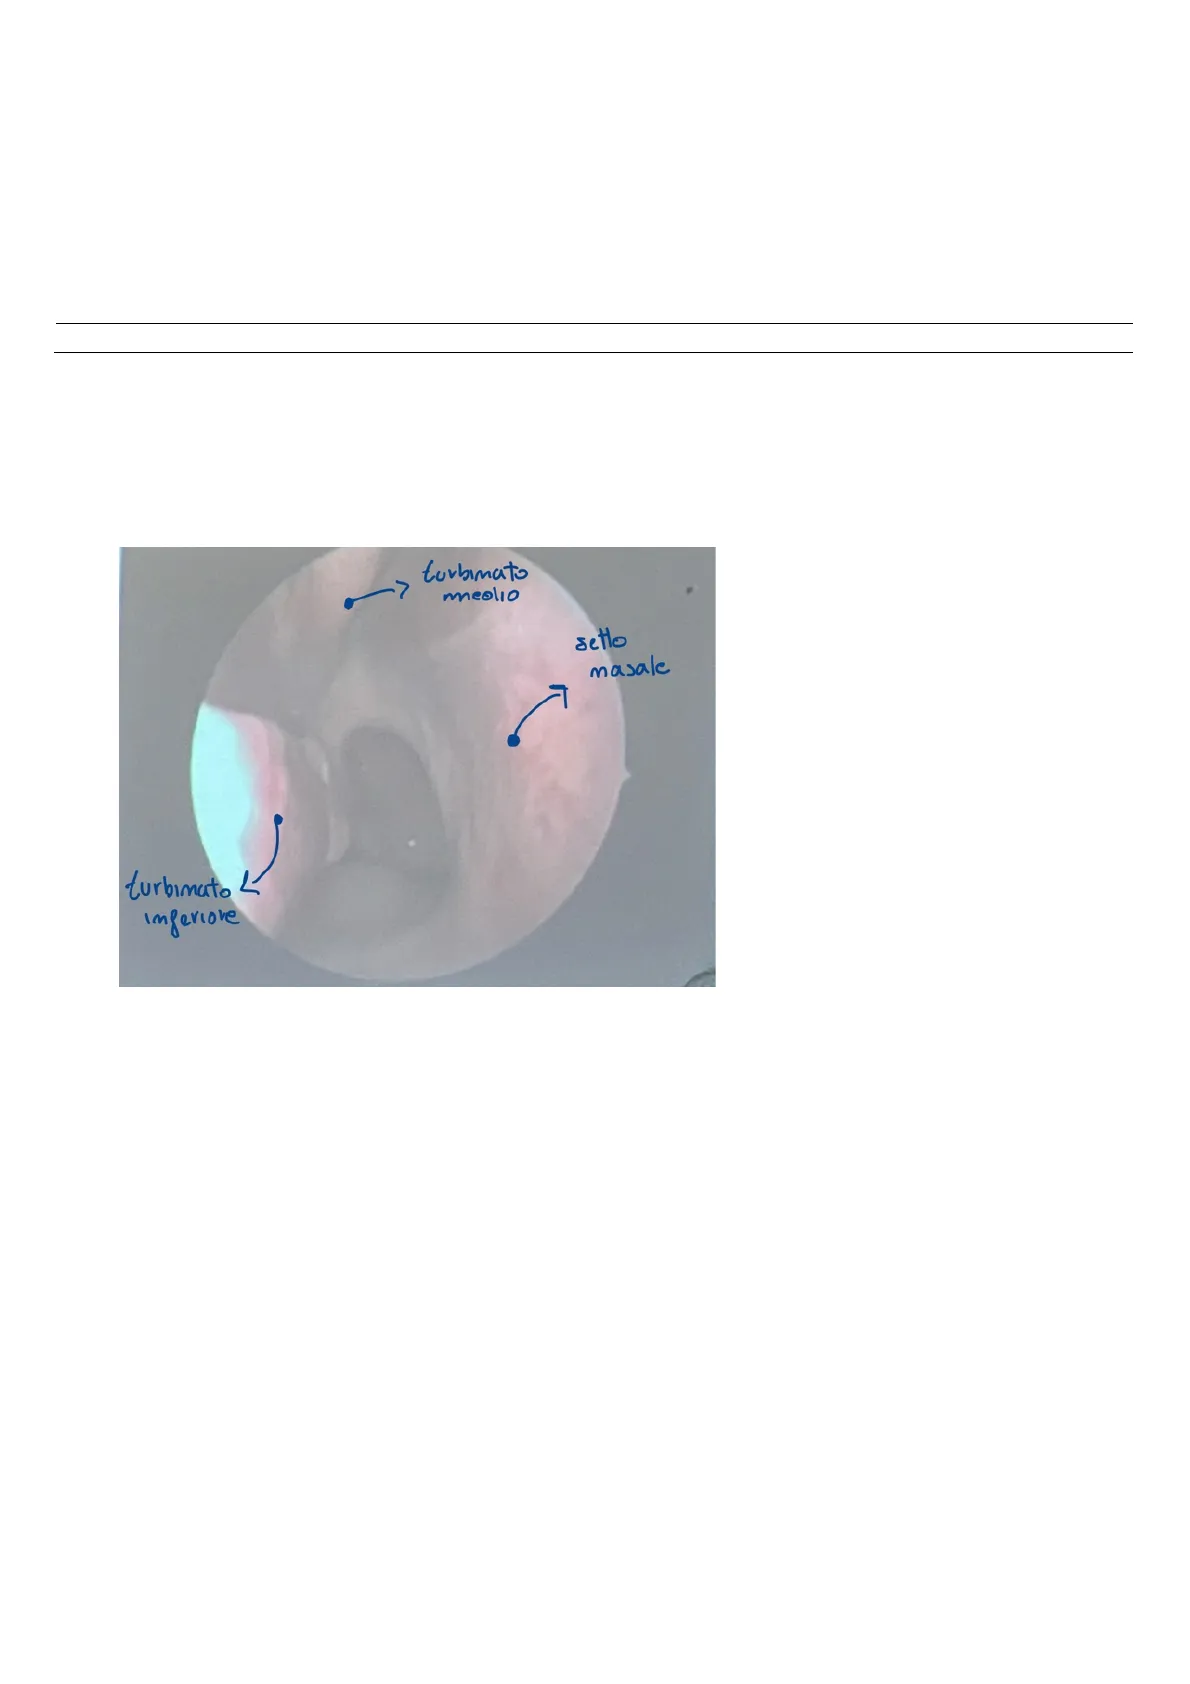

turbinato

medio

setto

masale

Inferiore

Mediante endoscopia delle fosse nasali

è possibile osservare tutta una serie di

strutture:

Il setto nasale è centrale e mediano ed

è una struttura osteo-cartilaginea che

separa le due fosse nasali. L'anatomia

Nell'immagine si osserva: il turbinato medio, quello

inferiore e il setto nasale.